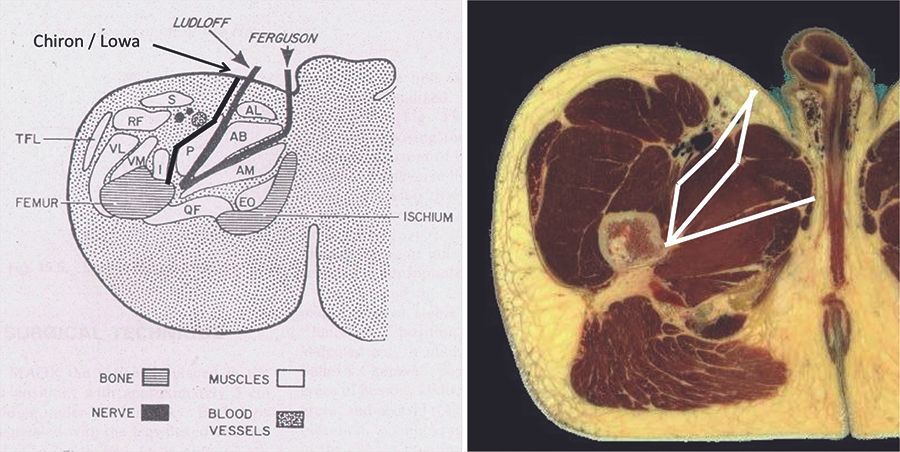

Technique La voie antéro médiale de la hanche chez l'adulte , Philippe Chiron Hôpital Pierre-Paul Riquet, Toulouse, France , Jérôme Murgier Département Orthopédie Traumatologie - CHU Toulouse - France N°278 - Novembre 2018 - Cahier 2 ● 10 min de lecture